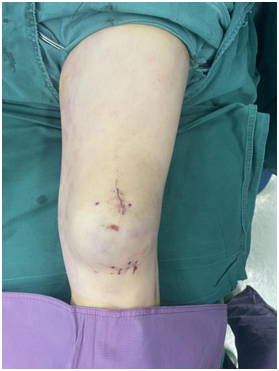

手术非常成功。目前文女士的膝盖上只留下了一个小小的疤痕。术后,她已经在骨科一病区团队的指导下,开始了早期的康复锻炼。虽然完全康复还需要一段时间,但微创手术带来的小创伤和快速恢复,让她对重新正常行走充满了信心。